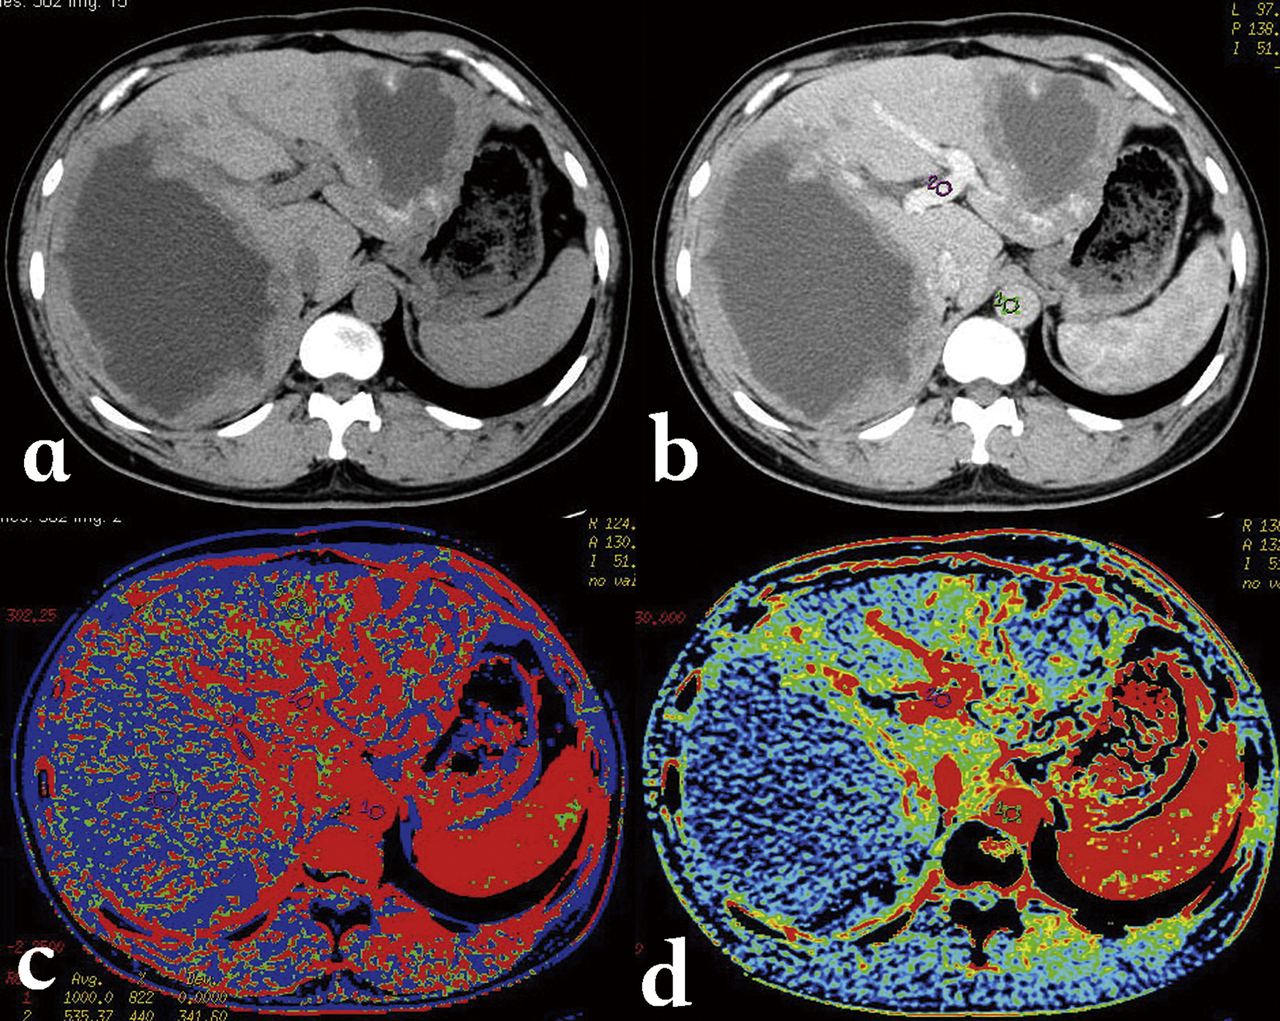

Liver phantom with multiple focal lesions including hemangioma, hepatocellular carcinoma, cyst, and metastasis for...